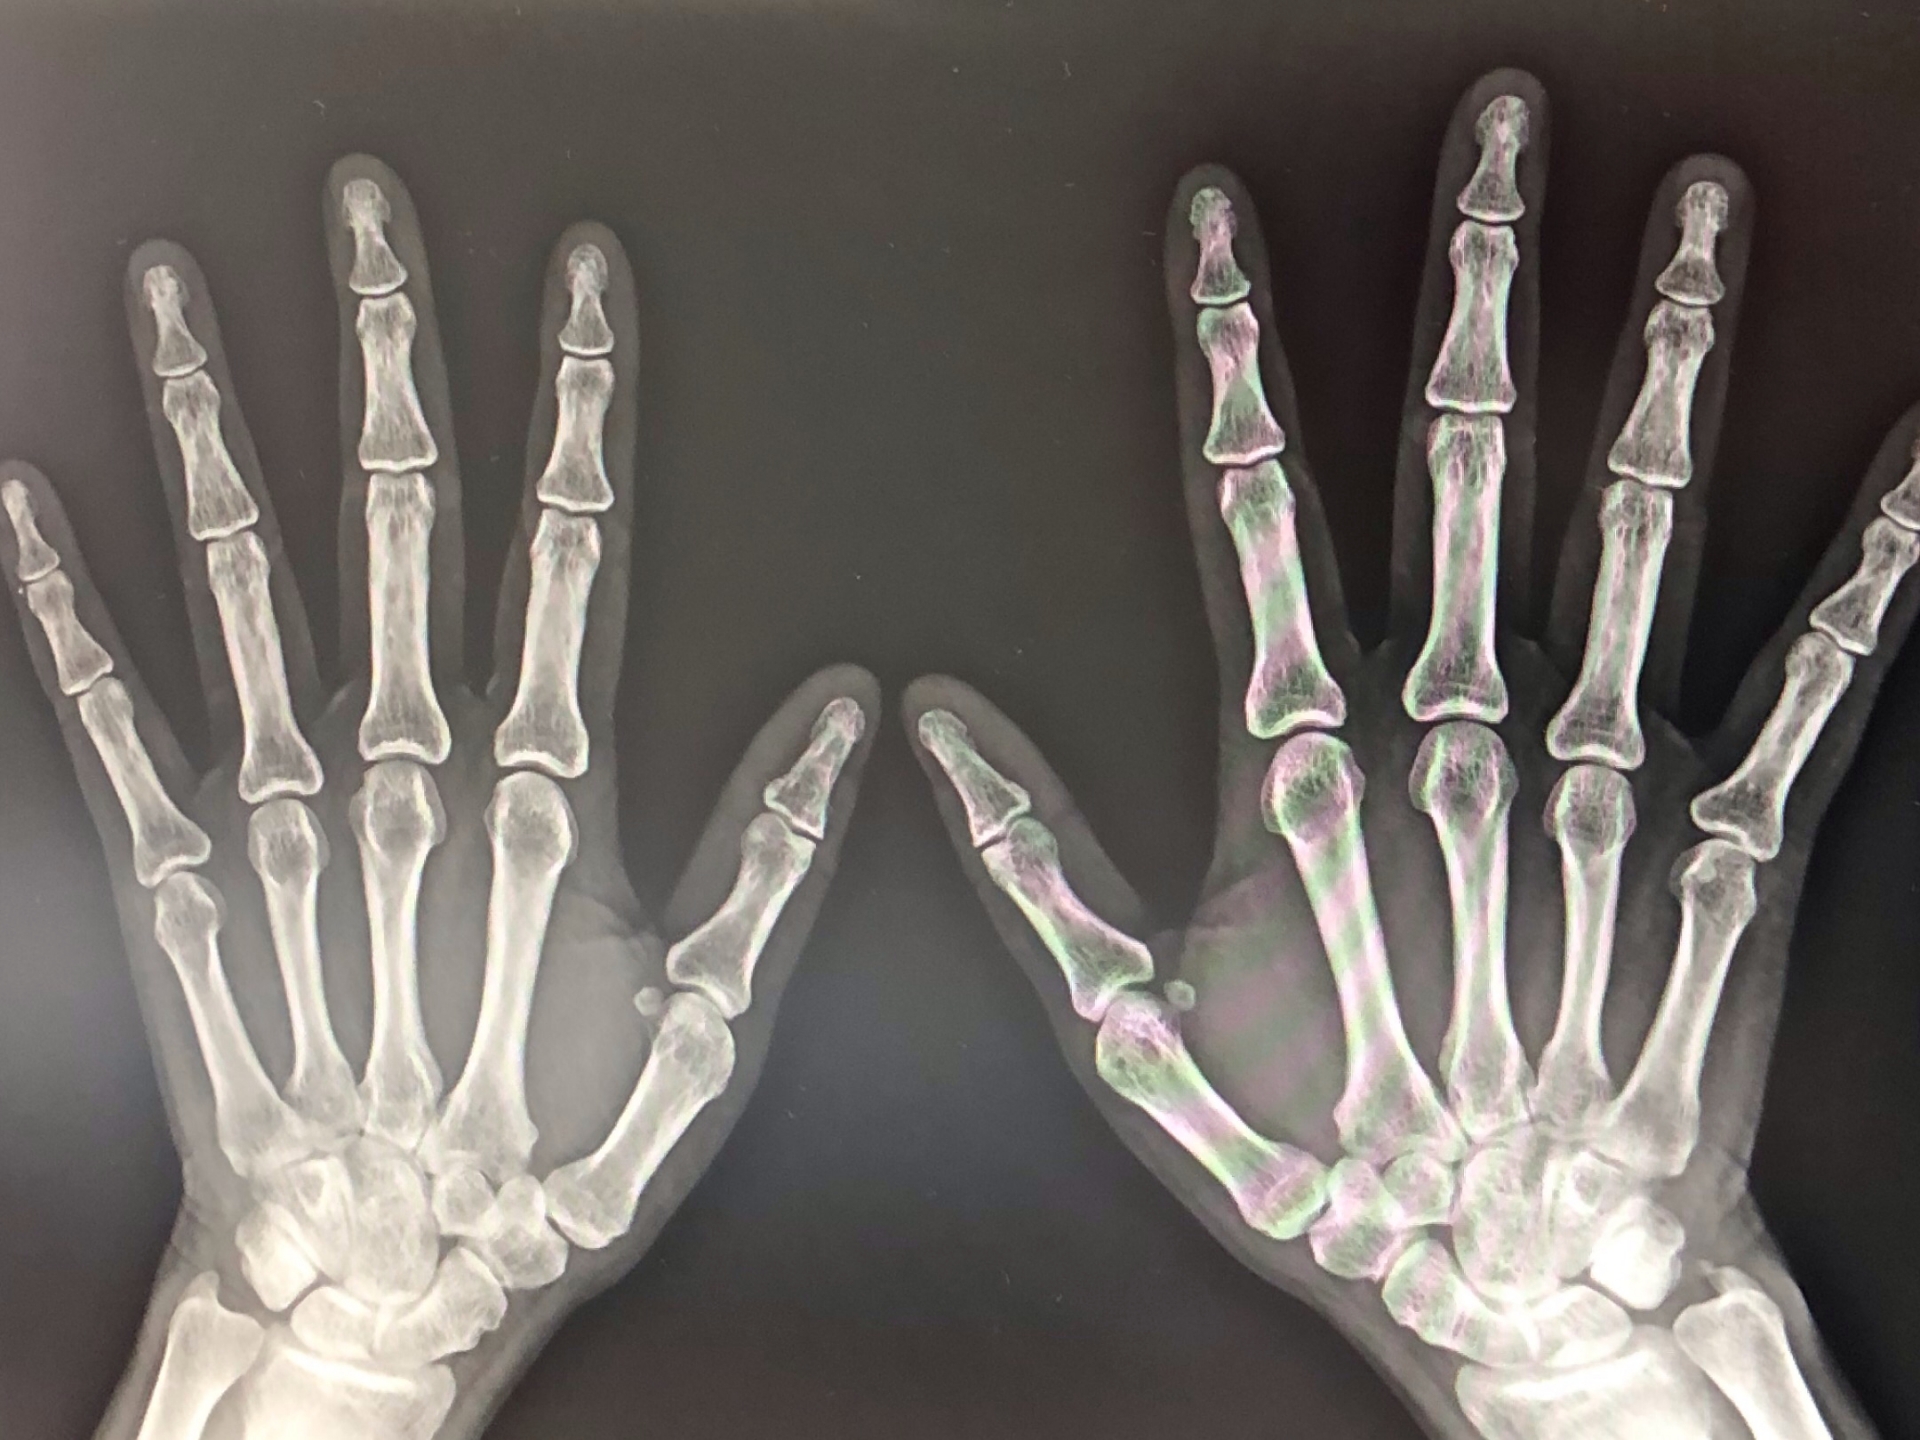

ホームズは昔の新聞を取り出してきて、ハザリーに見せた。そこには一年前に一人の水力技師が、夜の11時に下宿を出たきり行方不明になったと載っていた。ホームズたちはロンドン警視庁に行き、警部と刑事に同行してもらった。ハザリーの下りた駅に着くと近くの屋敷が燃えている。昨夜のうちに出火したらしい。ハザリーはその外観を見て、彼が行った屋敷に間違いないと言った。ホームズは12マイルの距離の秘密は、6マイル遠ざかって戻って来ただけと話す。その屋敷にはベッカー博士という英国人が住んでいるらしいが、泊まっている男は体形からしてファーガスンだろう。スターク大佐たちはニセ金作りの一味で、水圧機で棒金もどきを作っていたがその場所が分からなかったと警部が言う。火事の原因は水圧機で潰されたランプであろう。そして朝早く、箱を積み込んだ馬車が数人を乗せて出て行ったとの目撃情報があったが、その後の足取りはつかめなかった。鎮火してから、水圧機の残骸、大量のニッケルとスズ、そして切られた人間の親指が発見された。ハザリーが隠れて気絶した茂みには2人分の足跡があったので、心優しい婦人とファーガスンがハザリーを見つからないよう運び出したと思われた。儲けと親指を失くしたと嘆くハザリーに、ホームズは得たものは経験だと語った。